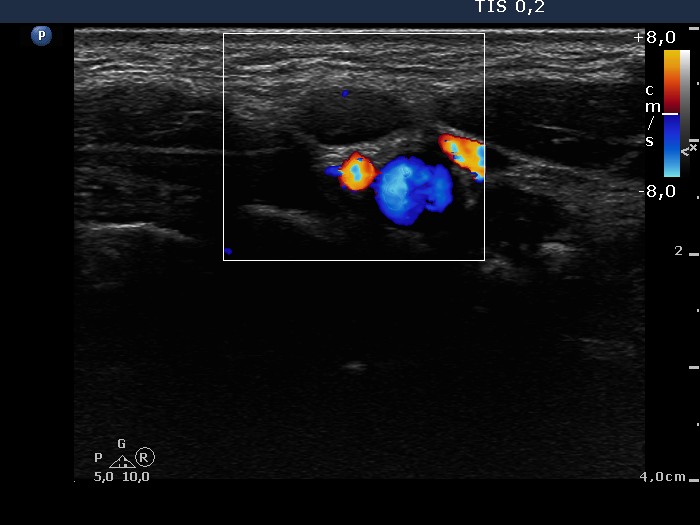

Lymph nodes - case conp 005 (ultrasonographic picture 8)

Left side of the neck, above the thyroid, transverse scan, color Doppler mode. There is no vascularization according to the lymph node.